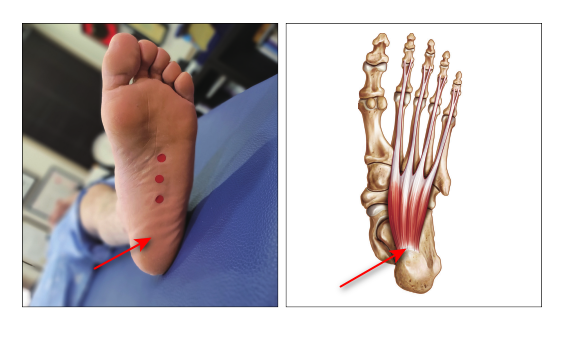

빨간색 동그라미 친

발바닥 뒷꿈치가 아픕니다.

빨간 화살표 부위를

손가락으로 눌러보세요

눌렀을 때 아프면

족저근막염일 확률이 높고요.

아프지 않다면

족저근막염이 아닐 수 있습니다.

지압 부위는

빨간색으로 표시한 곳입니다.

아프지 않는 선에서

가볍게!

꼭 가볍게만 눌러주세요.